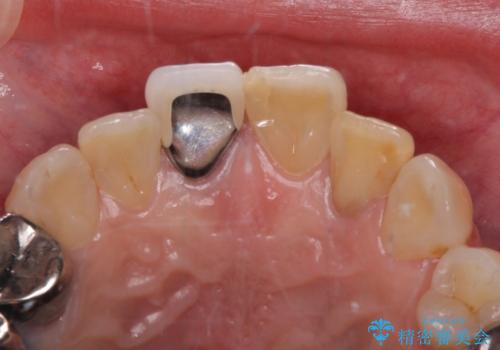

前歯は神経を取り除いて変色した歯や金属の縁が見える歯などがあり審美的に気になっていましたが、治療するかどうかは悩んでいらっしゃいました。

ところが、奥歯の治療を開始する前に、神経が失活して根尖部に病変のある前歯が著しく痛み出したため、根管治療を行うこととなりました。